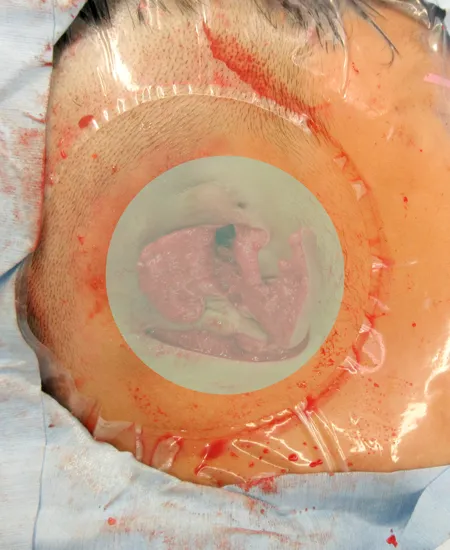

皮弁形成を行いました。

すべての遺残耳介軟骨を摘出しました。皮下ポケットを作成しました。

3次元肋軟骨フレームを皮下ポケットへ移植します。